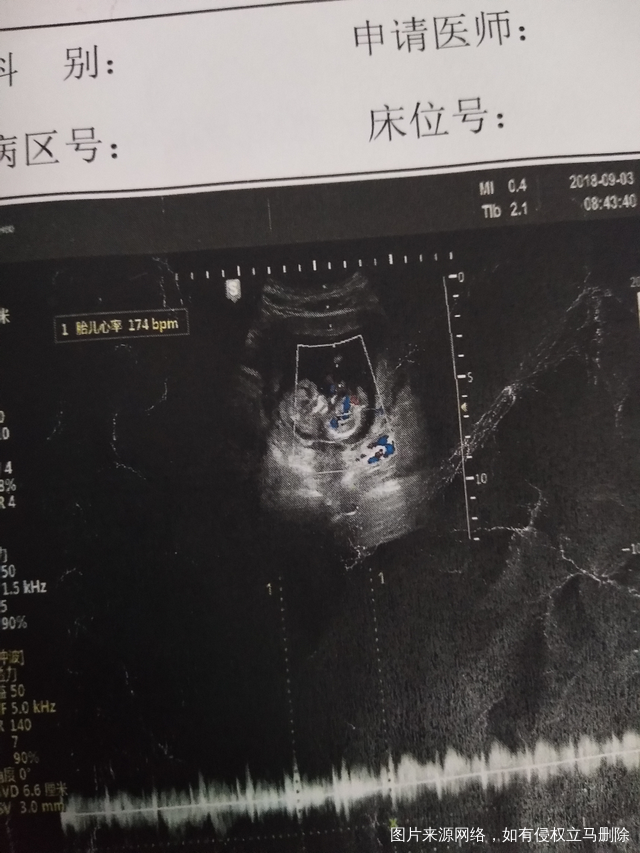

宝宝一路过来真的很坚强,去做完nt之后这两周又见了两次红,虽然多次见红,但每次我都吓得不轻,可能我就这体质吧!早唐也过了,很开心!就一个缺铁,宝宝很健康!!!谢谢亲们一直的鼓励!下面是12周照的!